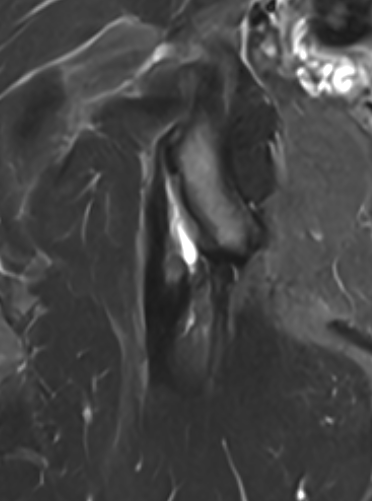

High grade partial tear proximal hamstring

High grade partial tear proximal hamstring